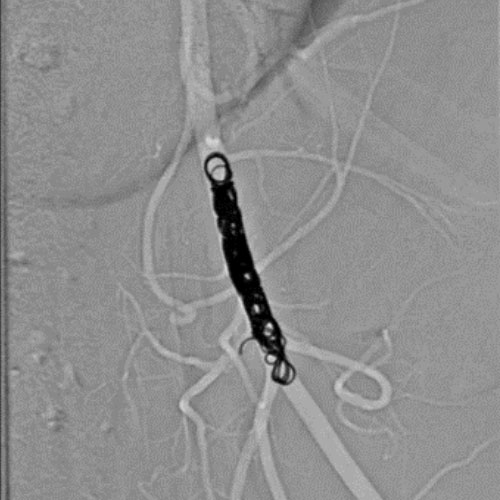

Embold Fibered Coil shown in left internal femoral artery Ruby Standard Coil shown in left internal femoral artery

Left internal femoral artery

5 Ruby Standard 6x20

Embold Fibered Coil shown in right internal femoral artery Embold Fibered Coil shown in right internal femoral artery

Right internal femoral artery

3 Embold Fibered Coil 6x20

5 vs 3 Coils